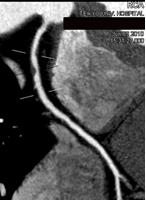

心臓・冠動脈CT

心臓の冠動脈に狭窄部位があるかどうかを評価したり心臓の奇形などを調べる検査です。

CTでのの心臓検査は、造影剤を静脈から注入し、冠動脈の状態を撮影します。